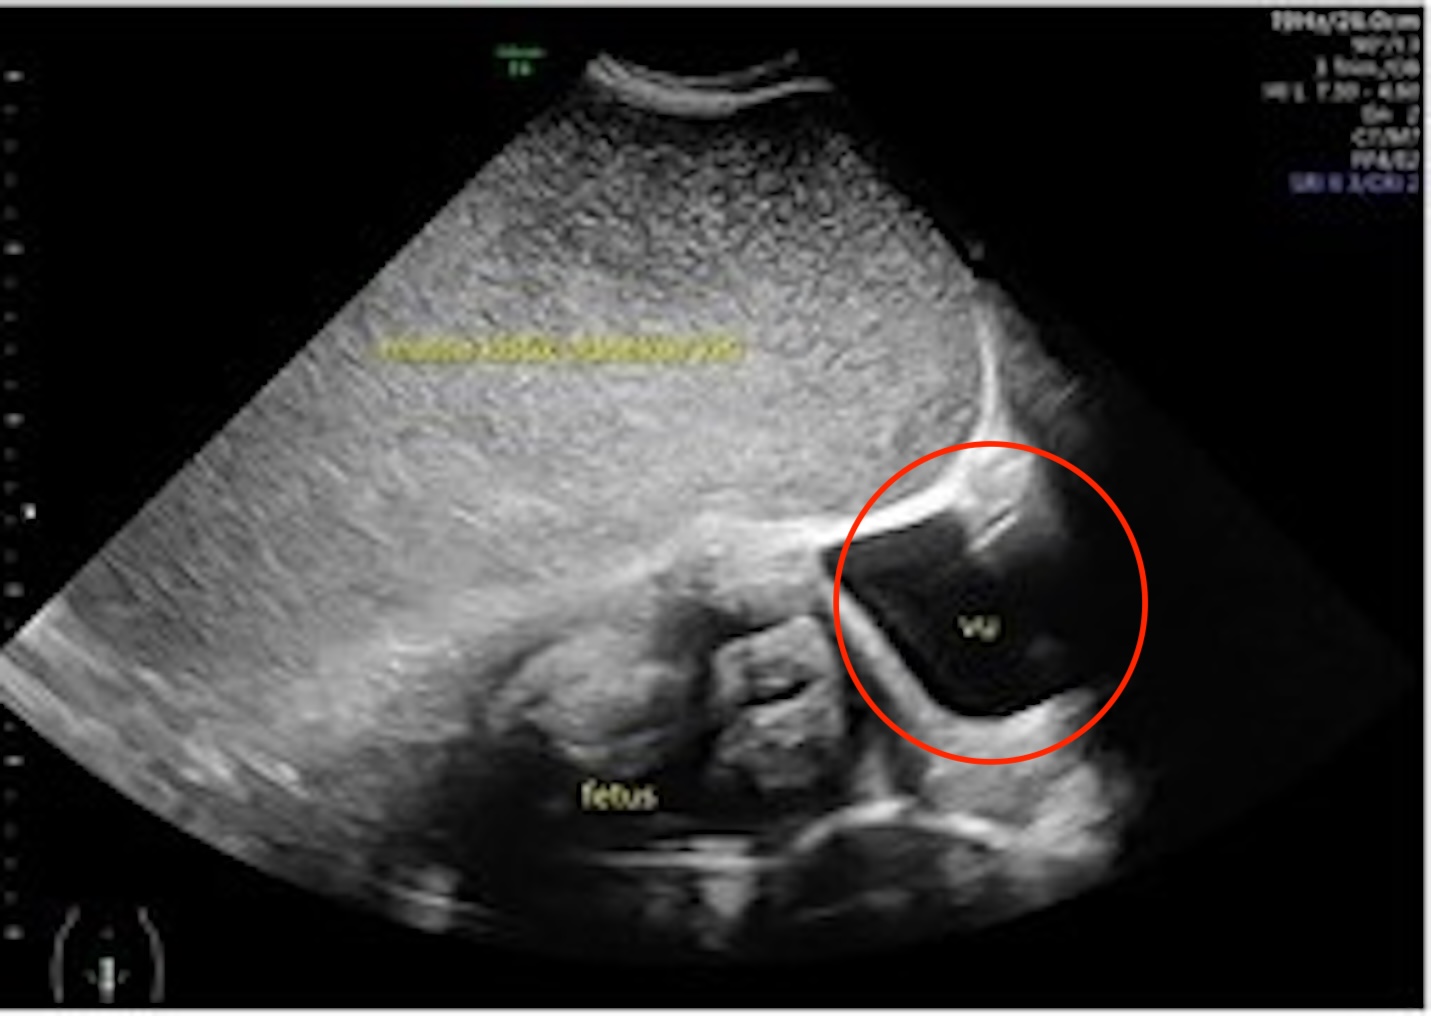

Những hình ảnh được chia sẻ bởi Need To Know cho thấy hình ảnh siêu âm khối u trước khi cắt bỏ.

Hình minh họa cho thấy vị trí của u nang, bao phủ một phần tử cung và đẩy sang một bên.